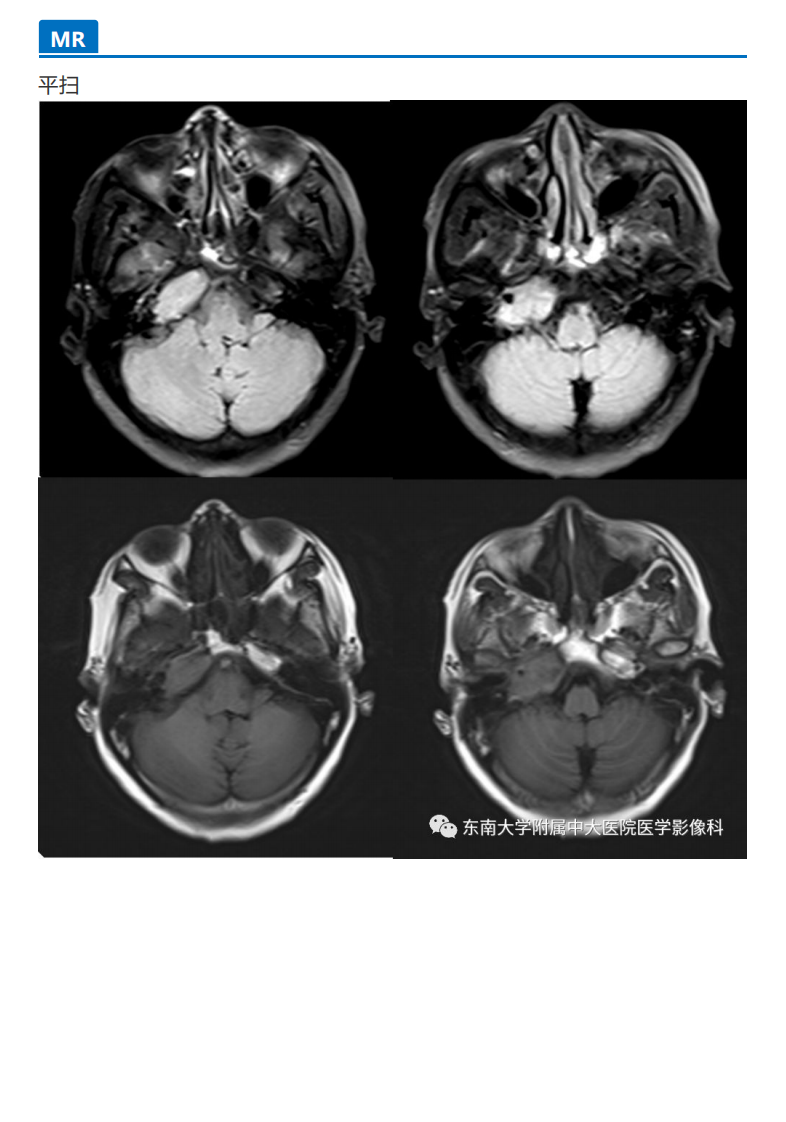

20190930_3【晨读结果公布】2019.09.29头颈部系统疾病.pdf